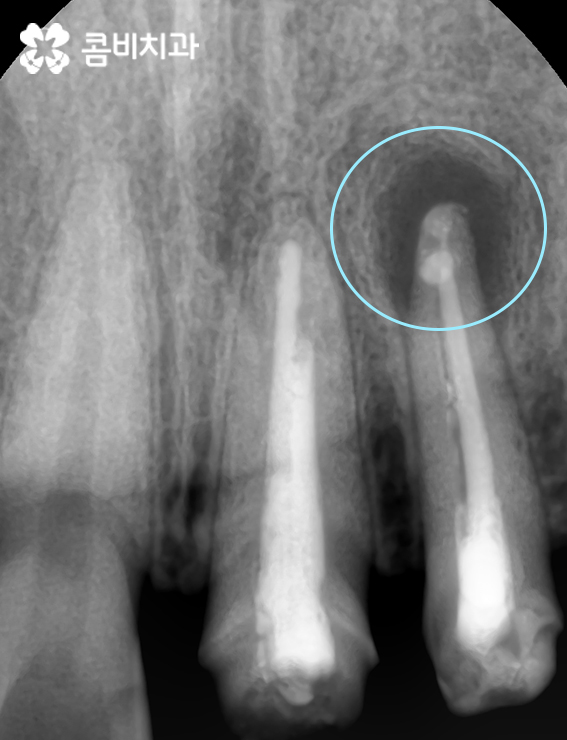

위 사진은 앞니신경치료 후 모습이며 염증의 크기는 시간이 경과하면서 조금씩 줄어들게 됩니다.

(시간이 경과하면서 염증이 상당 부분 줄어든 것이 확인이 됩니다.)